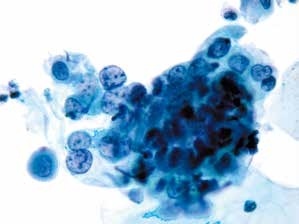

2. 非角化型鳞状细胞癌(non-keratinized squamous cell carcinoma)(图4-65~4-70)

图4-65 非角化型鳞癌(高倍、液基、巴氏染色)

明显的肿瘤素质,癌细胞成团,形态多样,核大,深染,染色质粗颗粒状,胞质蓝染。